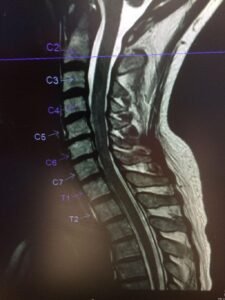

Как изглежда шийна спинална стеноза на ЯМР

ЯМР (магнитно-резонансна томография) е едно от най-точните изследвания за установяване на стесняване на гръбначния канал в шийната област.

При това изследване може да се види:

• степента на стесняване на гръбначния канал

• притискане на гръбначния мозък или нервните структури

• дискова херния във врата

• костни шипове (остеофити)

• дегенеративни промени в междупрешленните дискове

Тези промени могат да доведат до намаляване на пространството в гръбначния канал и до дразнене или притискане на нервните структури.